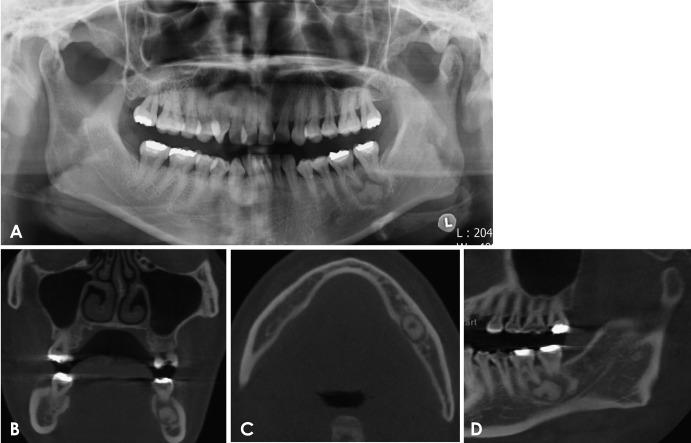

Ossifying fibroma is a slow-growing benign neoplasm that occurs most often in the jaws, especially the mandible. The tumor is composed of bone that develops within fibrous connective tissue. Some ossifying fibromas consist of cementum-like calcifications, while others contain only bony material; however, a mixture of these calcification types is commonly seen in a single lesion. Of the craniofacial bones, the mandible is the most commonly involved site, with the lesion typically inferior to the premolars and molars. Ossifying fibroma of the jaw shows a female predominance. Some reports of ossifying fibroma have been published in the literature; however, this report continues the research on this topic by detailing 3 types of ossifying fibroma findings on panoramic radiographs and cone-beam computed tomographic images of 4 patients. The radiographs of the presented cases could help clinicians understand the variations in the radiographic appearance of this lesion.

骨化性纤维瘤是一种生长缓慢的良性肿瘤,最常发生于颌骨,尤其是下颌骨。该肿瘤由在纤维结缔组织内形成的骨组织构成。一些骨化性纤维瘤由类牙骨质钙化组成,而另一些仅含有骨质材料;然而,在单个病变中通常可见这些钙化类型的混合。在颅面骨中,下颌骨是最常受累的部位,病变通常位于前磨牙和磨牙下方。颌骨骨化性纤维瘤以女性居多。文献中已发表了一些关于骨化性纤维瘤的报告;然而,本报告通过详细描述4例患者全景X线片和锥形束计算机断层扫描图像上的3种骨化性纤维瘤表现,继续对该主题进行研究。所呈现病例的X线片有助于临床医生了解该病变X线表现的差异。